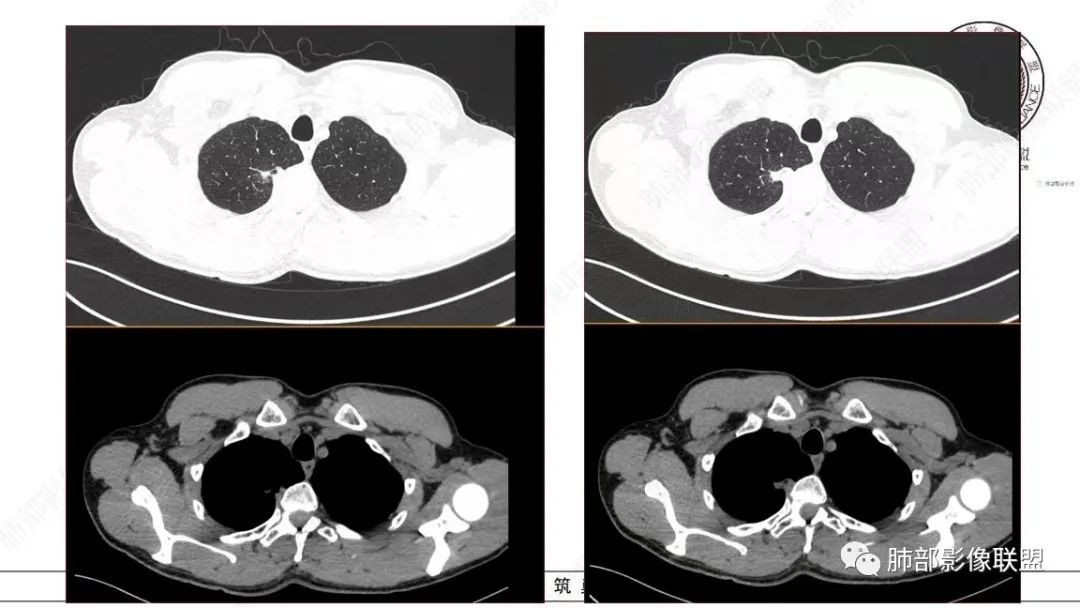

飞鹰行动:中年男性,右肺上叶不规则病灶,与胸膜粘连,多发长毛刺,周围模糊的磨玻璃影,相邻胸膜增厚,增强病灶中度以上强化,内见血管影,没有重建图像,感觉病灶符合良性病变征象多一些,考虑炎性病变,OP?

小兜:男,50岁,体检发现右肺上叶胸膜下不规则软组织结节,分叶,长毛刺,与胸膜相连,胸膜增厚,渐进性强化,强化不均匀,内部可见小灶状低强化灶,内部血管穿行。首先考虑肉芽肿性病变,鉴别腺癌

衡妈:中年男性,右肺上叶尖段不规则实性病灶,边缘多深分叶局部形似并见数条长毛刺,与胸膜面数条牵拉中年男性,右肺上叶尖段不规则实性病灶,边缘多深分叶局部形似枫叶,侧胸膜局部幕状增厚,病灶增强后不均匀中等强化。考虑恶性肿瘤,腺癌可能,鉴别炎性肉芽肿(结核)、炎性肌纤维母细胞瘤。

谢加平:右肺上叶尖段内侧胸膜下分叶状结节,不规则,见尖角状凸起,边缘支气管锥形中断,实性不均匀强化,血管进入增粗和集血管束特点,宽基底胸膜牵拉,形成兔耳征,冠状面结节外侧见指头状凸起,恶性特点明显,支持浸润性腺Ca。

仔细看,里面是有低密度的。平扫CT值也很低,才16HU。

增强也很有特点。这些低密度,是有延迟强化特点的。

平扫低密度,就这个病变而言,我们最容易想到的:干酪性坏死、黏液。而延迟强化。所以这个病变是不符合干酪性坏死的表现的。很多平直凹陷的地方,与胸膜宽基底接触,是否存在胸膜牵拉不详,需重建看看。说明这个病变是有收缩力的。里面含有一部分纤维。当然,含有纤维的,肿瘤的肌成纤维可以,上皮间质转换可以,慢性炎也可以,好多病变里面可以有纤维。干酪样坏死,是不会强化的。延迟强化,肉芽肿可以,纤维比较多的或者黏液多的也可以。